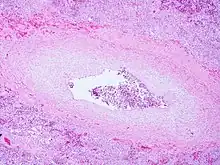

| Pulmonary veno-occlusive disease-Intimal fibrosis with marked narrowing of lumen of a large pulmonary vein | |